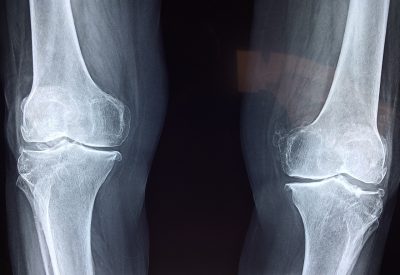

Czym jest Chondromalacja? Chondromalacja, znana również jako zespół bólowy rzepki, jest chorobą, która dotyczy stawu kolanowego. Polega ona na uszkodzeniu chrząstki stawowej znajdującej się na tylnej powierzchni rzepki (patella) – małej kości, która znajduje się na przedniej części kolana i…